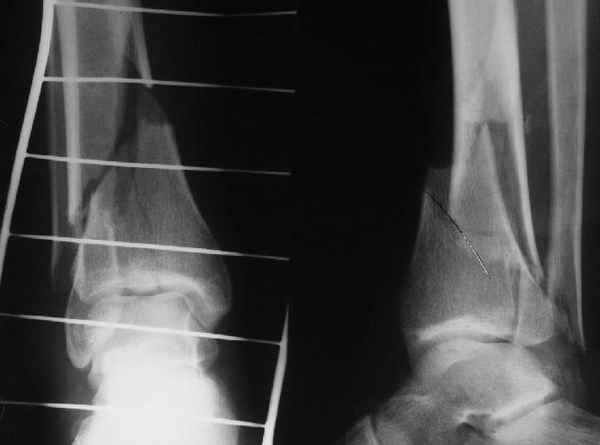

Re: ANKLE FRACTURE

Evgueny Tschekashkin 12 Сентябрь 2004, 15:08

I would suggest to fix the fibular fracture at the very beginning and under fluoroscopical control and axial traction try to restore articular surface stabilizing percutanously by K wires and cannulated screws, type of external fixation to be used is up to your preference.

Alexander Chelnokov 12 Сентябрь 2004, 15:11

Я вот все в толк не возьму смысл отдельной фиксации малоберцовой кости пластинкой, если все равно будет аппарат с фиксацией стопы, т.е. возможностью провести спицы в пятку, таран, наружную лодыжку и еще черт-те куда. Остеосинтез пластинкой выглядит логичным в случае, когда наружная фиксация планируется как временная. Но тут-то аппарат будет окончательным фиксатором.

Еще, кстати, о фиксации лодыжки, если уж непременно хочется ее отдельно стабилизировать - при таком характере перелома замечательно должен сработать предложенный проф. Лазаревым с соратниками способ фиксации напряженной V-образной спицей. Опять же, открытая репозиция не нужна, мы делаем непрямую репозицию именно аппаратом. В приложении пример, там перелом малоберцовой куда менее поперечный, чем в данном случае, но все равно получилось закрыто без пластинки.

I can't realize why plate fibula separately if anyway external fixator including the foot is planned, i.e. one may insert wires to the talus, calcaneus, lateral malleolus and anywhere else. Plating looks reasonable if only temporary ex-fix is planned, but in the case it will be definitive.

A propos fibular fixation if one is eager to stabilize it separately. In the fracture pattern a way of closed fixation by V-shaped stressed wire (advanced by colleagues from Moscow, prof. Lazarev A.F. et al.) must be excellent. We use indirect closed reduction by the external fixator. Example attached, that fibular fracture is even more suitable for plating but the wire did the job.